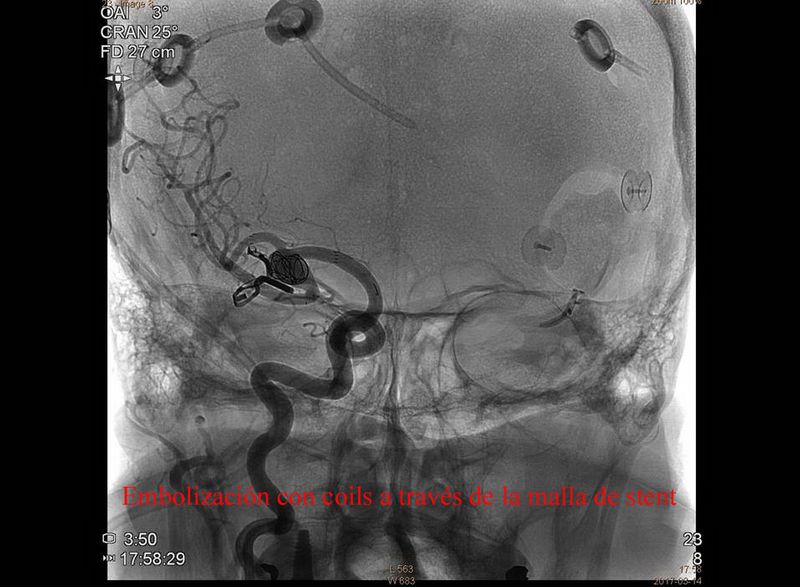

Aneurisma trat quirurgicamente